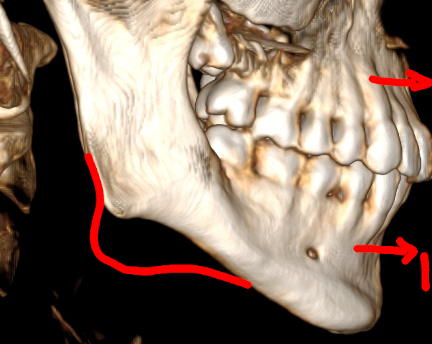

CBCT (Front + Side) + OPG (Old Before & New After braces) (need decompensation)

- Gonial Angle: 131.8°

- Bimax (BSSO + Lefort 1) with CCW Rotation: I need to close that 132° angle and get projection.

- Skeletal Expansion (MARPE/MSE/FME/SARPE): My inter-molar width is ~34.7mm. I’m debating and honestly I don't have much knowledge about this. I want to maximize midface widening and cheekbone support. Given I'm planning Bimax anyway, which one would you guys suggest?

- Midface support: I’m leaning towards custom PEEK inframalar/infraorbital implants but I want to know if I can avoid paranasal implants by performing a High LeFort I cut and advancing the ANS, or maybe eventually both?

- Genioplasty: Undecided. If the CCW rotation provides enough projection, I might skip it, but idk tbh.